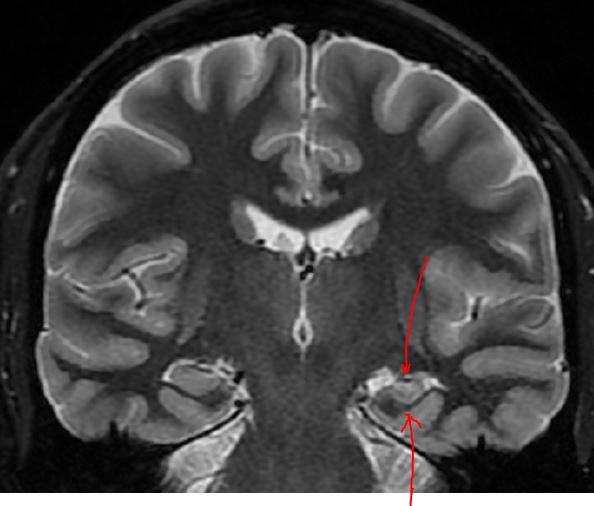

The MRI demonstrates atrophy of the body of the left hippocampus in the image above, with increased signal on this T2 weighted image stop